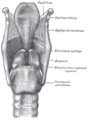

In front of the upper trachea lies connective tissue and skin.[1] Several other structures pass over or sit on the trachea; the jugular arch, which joins the two anterior jugular veins, sits in front of the upper part of the trachea. The sternohyoid and sternothyroid muscles stretch along its length. The thyroid gland also stretches across the upper trachea, with the isthmus overlying the second to fourth rings, and the lobes stretching to the level of the fifth or sixth cartilage.[1] The blood vessels of the thyroid rest on the trachea next to the isthmus; superior thyroid arteries join just above it, and the inferior thyroid veins below it.[1] In front of the lower trachea lies the manubrium of the sternum, the remnants of the thymus in adults. To the front left lie the large blood vessels the aortic arch and its branches the left common carotid artery and the brachiocephalic trunk; and the left brachiocephalic vein. The deep cardiac plexus and lymph nodes are also positioned in front of the lower trachea.[1]

Behind the trachea, along its length, sits the oesophagus, followed by connective tissue and the vertebral column.[1] To its sides run the carotid arteries and inferior thyroid arteries; and to its sides on its back surface run the recurrent laryngeal nerves in the upper trachea, and the vagus nerves in the lower trachea.[1]

The sternohyoid and sternothyroid muscles lie on top of the upper part of the trachea